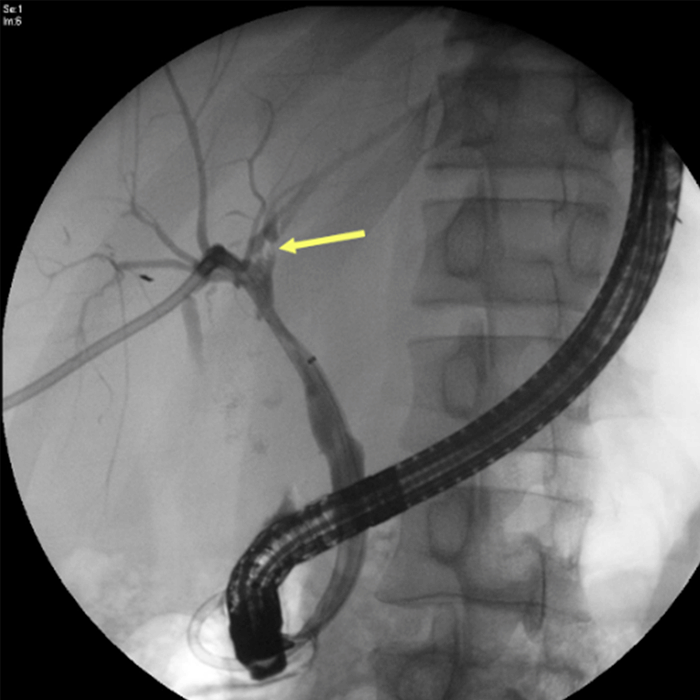

The patient's abdomen was eventually closed over drains on hospital day 13. Two weeks after his injury, he developed high bilious output (approximately 800 cc/day) from his right upper quadrant drain. An ERCP was performed, which demonstrated complete disruption of the right anterior hepatic duct at the bifurcation and a leak from the left intrahepatic bile duct (Figure 3).

Figure 3. Endoscopic Retrograde Cholangiopancreatography. Published with Permission

A) Bile leak from left intrahepatic duct; B) bile leak from right hepatic duct near bifurcation